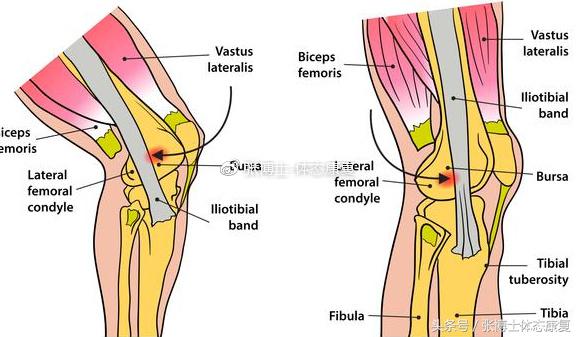

髂胫束结构

髂胫束位于阔筋膜的外侧部,是大腿的深筋膜结构,外形呈扁带状,起自髂嵴前份的外侧,其上部为两层,包裹阔筋膜张肌,下部为上述两层愈合而成,形成上宽下窄的腱性结构,向下延续,走行于大腿外侧,其远段跨过股骨外侧髁,末端止于胫骨前方外侧面。髂胫束可分为浅层、深层和被膜骨性层。分离浅层后可见深层纤维紧密粘附于股骨外侧髁并续于骨外侧肌间隔。其被膜骨性层起于外侧肌间隔和腓肠肌、跖肌后外侧筋膜,与股二头肌短头腱膜相延续,在膝关节前外侧形成吊带样结构。髂胫束止于胫骨前,部分前方纤维加入髌骨外侧支持带,即为髂髌束,部分后方纤维止于股骨外侧髁。

髂胫束是膝后外侧复合结构浅层的一部分,膝关节后外侧结构分为静力装置和动力装置。动力装置包括股二头肌腱、髂胫束、腓肠肌外侧头,其功能在膝关节运动时除了屈膝以外还协同静力装置限制胫骨外旋及膝内翻,大大加强了膝关节后外侧的稳定性。